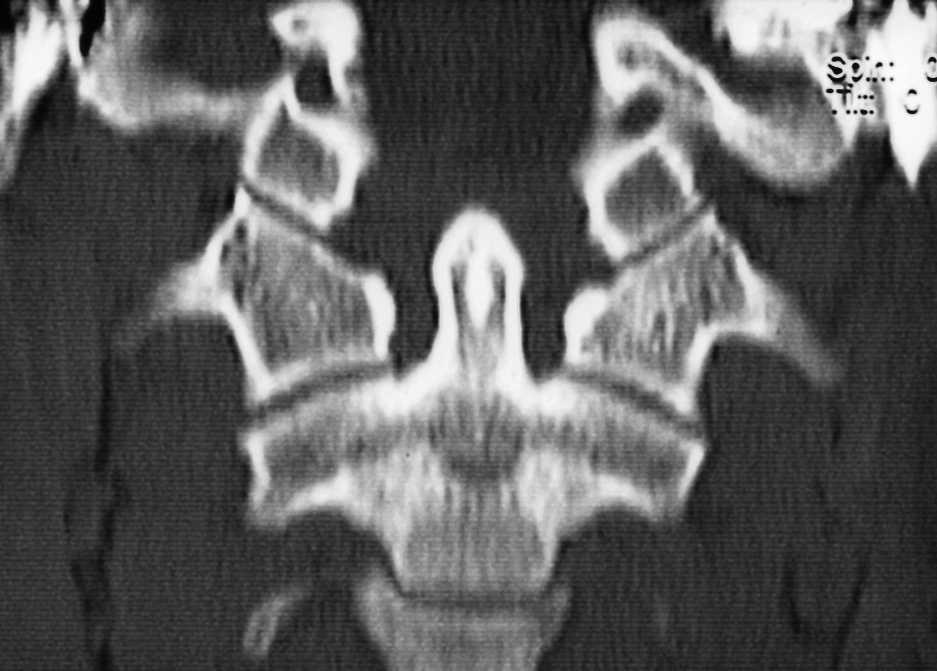

Niño de 7 años de edad con historia de tortícolis fija de 17 semanas de evolución a raíz de una infección respiratoria superior; antes de ser remitido, fue tratado mediante antiinflamatorios no esteroideos (AINE), ortesis cervical tipo Schanz y tracción elástica seguida de ortesis cervical sin resultado positivo. Mediante TAC se diagnosticó de SRCAA ipo I con una divergencia de 25° (fig. 4) y se inició un tratamiento con tracción hasta llegar a 8 kg, a las 3 semanas presentó unas rotaciones simétricas y la TAC (fig. 5) mostró una reducción completa, por lo que se inmovilizó mediante halo-yeso que se mantuvo 6 semanas, continuándose el tratamiento 6 semanas más con ortesis cervical blanda. Ocho años después, la función es normal, no presentando secuelas.

Figura 4. Tomografía axial computarizada donde se puede apreciar la deformidad rotacional del complejo C1-C2 en el segundo paciente con angulación de 25°.

Figura 5. Reconstrucción de la tomografía axial computarizada de control 3 semanas después, donde se aprecia la simetría entre la apófisis odontoides y las masas laterales del atlas con corrección completa de la rotación.